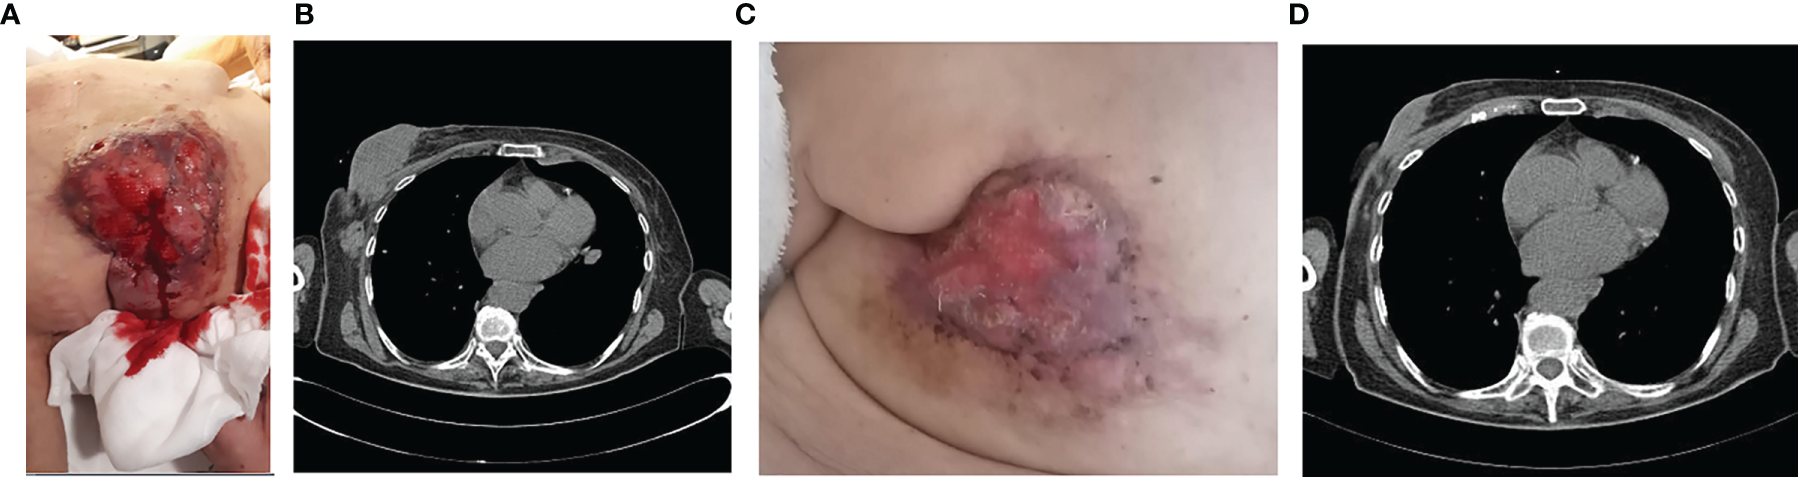

The radiograph shows the presence of a pathological fracture of the left humerus with an associated suspected bone lesion. A breast ultrasound revealed a nodular formation of about 20 mm in the right upper-internal quadrant and at least three pathological lymph nodes in the ipsilateral axilla. The biopsy confirmed the diagnosis of ductal breast carcinoma G2 ER 98% PR 98% HER2 negative, Ki-67 10%. The staging procedure with a CT scan and a bone scan confirmed the presence of a LABC with a single bone metastasis in the left humerus (Figures 4A, B). In April 2019, a bone biopsy was performed and the histological exam showed breast cancer cells with a profile ER 98% PR 80% HER2 1+ Ki67 8%. No surgical indication was given in consideration of the presence of reparative phenomena, the mild controlled pain, and the availability of active systemic treatments.

Figure 4

Imaging of bone lesion in the left homerus (A), and the locally advanced breast cancer at the time of diagnosis in March 2019 (B) and after 6 months of treatment (C).

Therefore, in May 2019, she started a first-line treatment with ribociclib 600 mg for 21 days/28-day cycle plus letrozole 2.5 mg/die plus triptorelin 3.75 mg every month. After the first 3 months, the patient had a clinical benefit and no pain in the left arm and the clinical examination revealed a significant reduction of the right breast lesion. A breast ultrasound showed a significant reduction of the target breast lesion (from 20 to 10 mm) and lymph nodes. The patient continued CDK4/6i plus letrozole. At 6 months, a CT scan showed a significant reduction of primary breast cancer (Figure 4C) and the single bone lesion with an overall partial response. No significant toxicity was observed, and the patient continued CDK4/6i + IA. In November 2020, after 18 months of treatment, CT scan confirmed the reduction of primary cancer and a stability of the bone lesion. The case was discussed in the breast multidisciplinary unit: considering objective response and the presence of a single bone lesion, it was decided for surgery on primary tumor and radiotherapy on the left humerus metastasis. On December 15th, the patient underwent right lumpectomy plus axillary lymph node dissection (ALND). The histological examination showed 19 × 10 mm IDC with 4/6 metastatic lymph nodes G2 ER 98% PR 0 Her2 0/1+ Ki67 2% pT1c pN2a (4/6). After 20 days, the patient resumed CDK4/6i + IA and triptorelin. In February 2021, a definitive 30-Gy radiotherapy on the single bone lesion was performed with concomitant CDK 4/6i + AI. The patient, after 32 months, is currently still on first line treatment with ribociclib + letrozole + triptorelin with no evidence of locoregional recurrence or systemic disease progression. The treatment was well tolerated during the entire period.